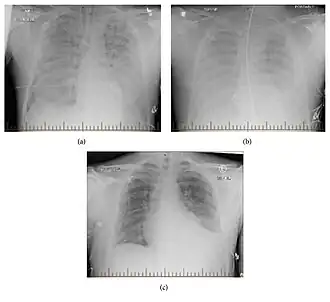

Progression to the Cardiopulmonary Phase

Within 4-10 days of infection, patients may begin to experience severe respiratory symptoms as the infection progresses.[7] These symptoms can include cough, shortness of breath, tightness of the chest, and rapid onset of pulmonary edema. Fluid buildup in the lungs caused by vascular leakage via viral disruption of endothelial blood vessel cells can lead to respiratory failure if untreated.[7]